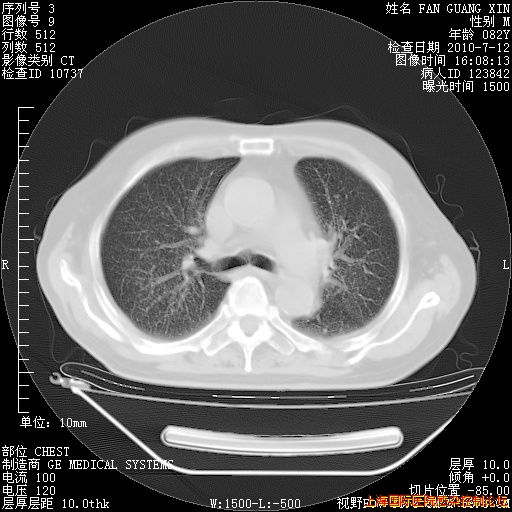

今天CT

整整相隔30天的肺部CT好像有所好转啊。甲强龙减量第3天,需要观察体温。